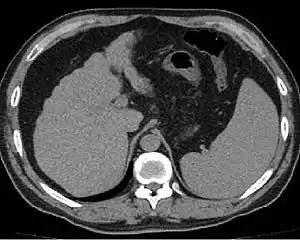

![]() Ознаки цирозу печінки на знімку комп'ютерної томографії. Ознаки цирозу печінки на знімку комп'ютерної томографії. | |